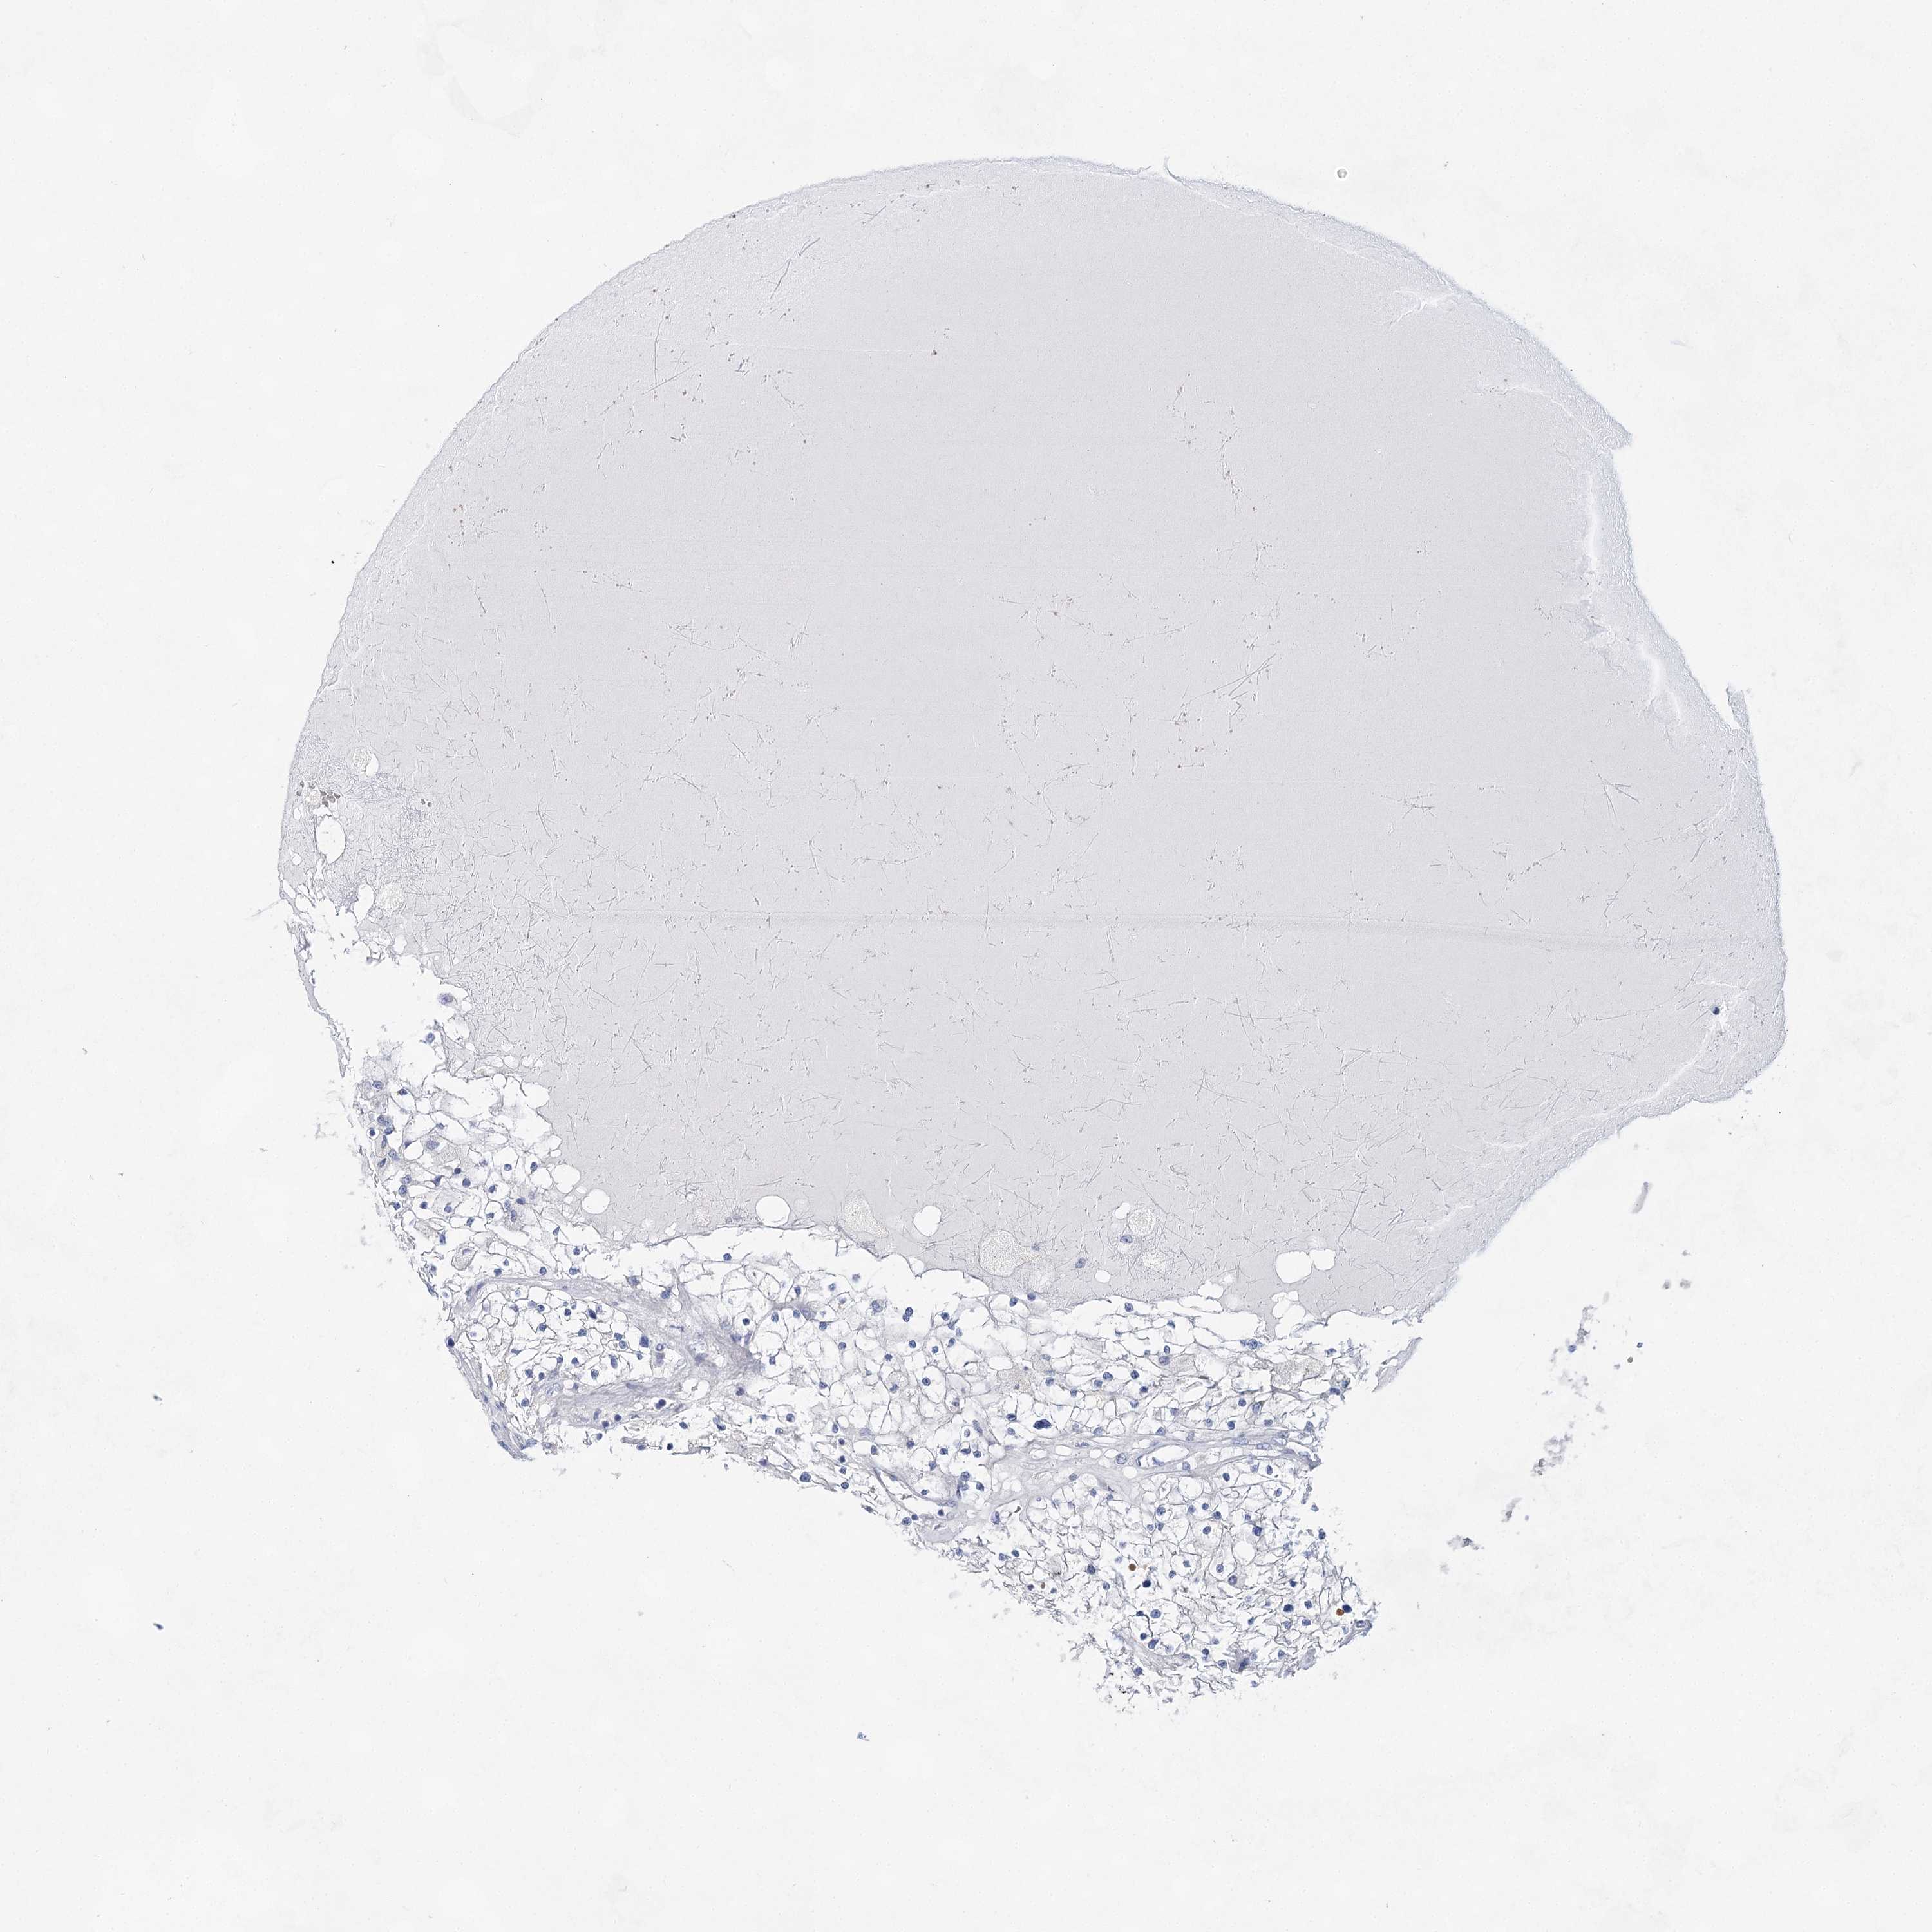

KIDNEY RENAL CLEAR CELL CARCINOMA (VALIDATION) - Interactive survival scatter ploti

The Survival Scatter plot shows the clinical status (i.e. dead or alive) for all individuals in the patient cohort, based on the same data that underlies the corresponding Kaplan-Meier plots. Patients that are alive at last time for follow-up are shown in blue and patients who have died during the study are shown in red.

The x-axis shows the expression levels (FPKM) of the investigated gene in the tumor tissue at the time of diagnosis. The y-axis shows the follow-up time after diagnosis (years). Both axes are complimented with kernel density curves demonstrating the data density over the axes. The top density plot shows the expression levels (FPKM) distribution among dead (red) and alive patients (blue). The right density plot shows the data density of the survived years of dead patients with high and low expression levels respectively, stratified using the cutoff indicated by the vertical dashed line through the Survival Scatter plot. This cutoff is automatically defined based on the FPKM cutoff that minimizes the p-score. The cutoff can be changed by dragging the vertical line or by entering a cutoff value in the square labeled "Current cut-off".

Under the Survival Scatter plot the p-score landscape (black curve; left axis) is shown together with dead median separation (red curve; right axis). Dead median separation is the difference in median mRNA expression between patients who have died with high and low expression, respectively. It is calculated as follows: median FPKM expression of dead patients with high expression - median FPKM expression of dead patients with low expression. This is intended to aid the user in visually exploring custom cutoffs and the associated p-scores and dead median separation.

Individual patient data is displayed and can be filtered by clicking on one or more of the category buttons on the top of the page. Categories describing expression level and patient information include: high, low, alive, dead, female, male and tumor stages. The scale of the x-axis can be toggled between linear and log-scale by clicking on the "x log" button. Mouse-over function shows TCGA ID, patient information and mRNA expression (FPKM) for each patient.

& Survival analysisi

Kaplan-Meier plots summarize results from analysis of correlation between mRNA expression level and patient survival. Patients were divided based on level of expression into one of the two groups "low" (under cut off) or "high" (over cut off). X-axis shows time for survival (years) and y-axis shows the probability of survival, where 1.0 corresponds to 100 percent.

BPHL is validated prognostic, high expression is favorable in Kidney Renal Clear Cell Carcinoma (validation)

: 11.32

Average pTPM 22.8

Number of samples 100